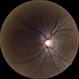

- glaucomatous atrophy of optic disc

- A 67-year-old glaucomatous patient presented and optic disc changes had laminar dots and peri pappilary atrophy.